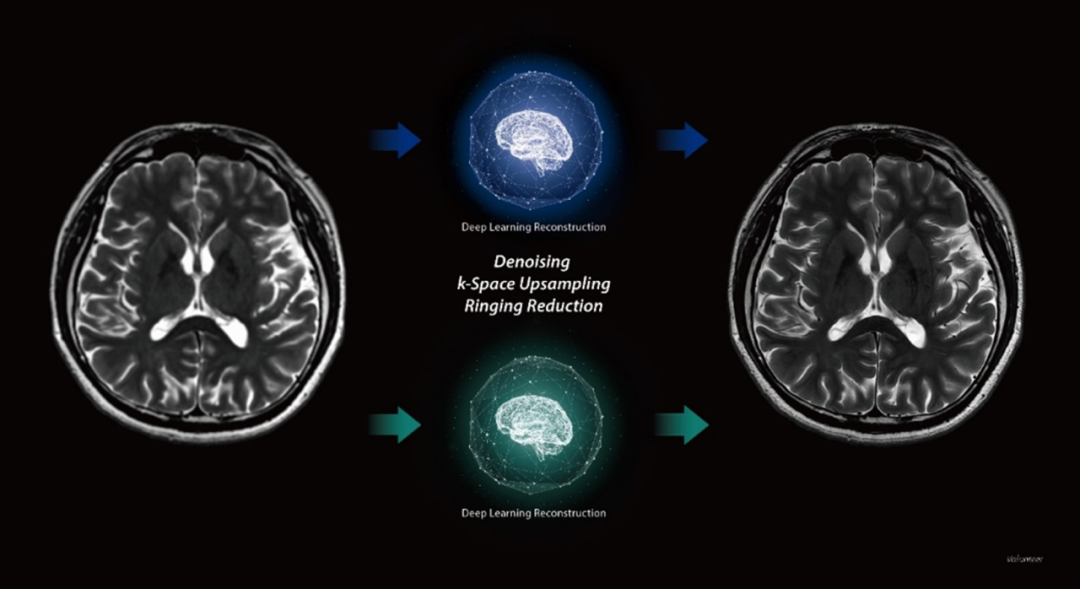

在磁共振领域,深度学习技术对图像进行降噪、上采样、减轻振铃伪影的处理,带来了清晰且细节丰富的图像。

过去,高分辨率图像的获取往往伴随着漫长的扫描时间,这影响了图像获取的效率,对于危重疾病的快速诊断是一大挑战。然而,PIQE技术的出现彻底颠覆了这一局面。此次发布的全新3T磁共振Galan Supreme,搭载全新的自研磁体和梯度线圈,并深度融合PIQE技术,可以实现在不增加扫描时间的前提下,轻松获取到高分辨率的图像,为临床带来了兼具高效与高质量的影像体验。